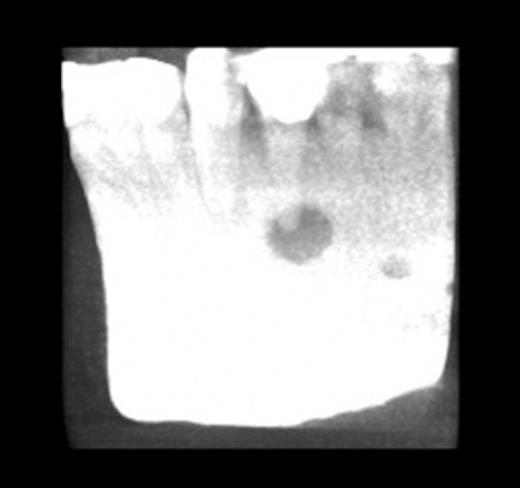

Plain radiographs revealed a periapical radiolucency of the lower left first premolar. A gutta percha (GP) point was inserted into the sinus. Cone beam computed tomography (CBCT) showed the GP point to be in communication with the periapical area (Fig. 3 & 4).

CT showing gutta percha point communicating with the periapical area